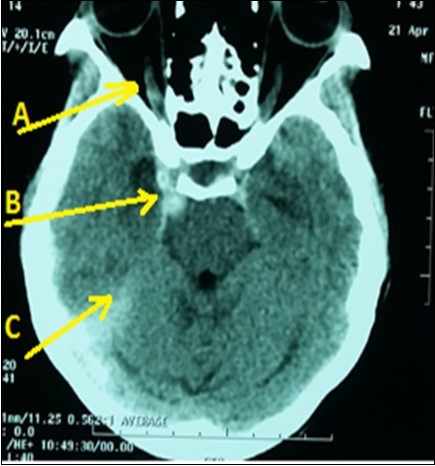

A 43-year lady, right-handed, single and mother of two children, was admitted in emergency neurology for intense headaches with vomiting, 2 generalized seizures and a sudden onset of consciousness disorders on April 19, 2016. Symptoms began two hours before her admission. She had no vascular history. The physical examination revealed intense headaches. The blood pressure was 130/80 mmHg with normal temperature (36.8 ° C). There was a light comas status with a Glasgow score of 12/15, a stiff neck, left hemiparesis and a bilateral Babinski reflex, right ptosis associated with reactive mydriasis, an exophthalmos and a total right ophthalmoplegia. Ophthalmologic examination revealed a right visual acuity of 1/10 with macular chorioretinitis. The brain CT scan (Figure 1) displayed a dilatation and hyper-density of right cavernous sinus with dilatation of the right ophthalmic vein associated with a subarachnoid hemorrhage. The routine biological tests were normal. An analgesic treatment had been administered in addition to nimodipine and mannitol (against brain edema) and clonasepam (against seizures). Unfortunately, as interventional neuroradiology and arteriography are not available, the patient had died on the seventh day of hospitalization in a context of increased intracranial hypertension.

Figure 1.Brain CT scan displaying right CCF (Arrow B) with subarachnoid hemorrhage (Arrow C) and right ophtalmic vein dilatation (Arrow A)

Brain CT scan displaying right CCF (Arrow B) with subarachnoid hemorrhage (Arrow C) and right ophtalmic vein dilatation (Arrow A)